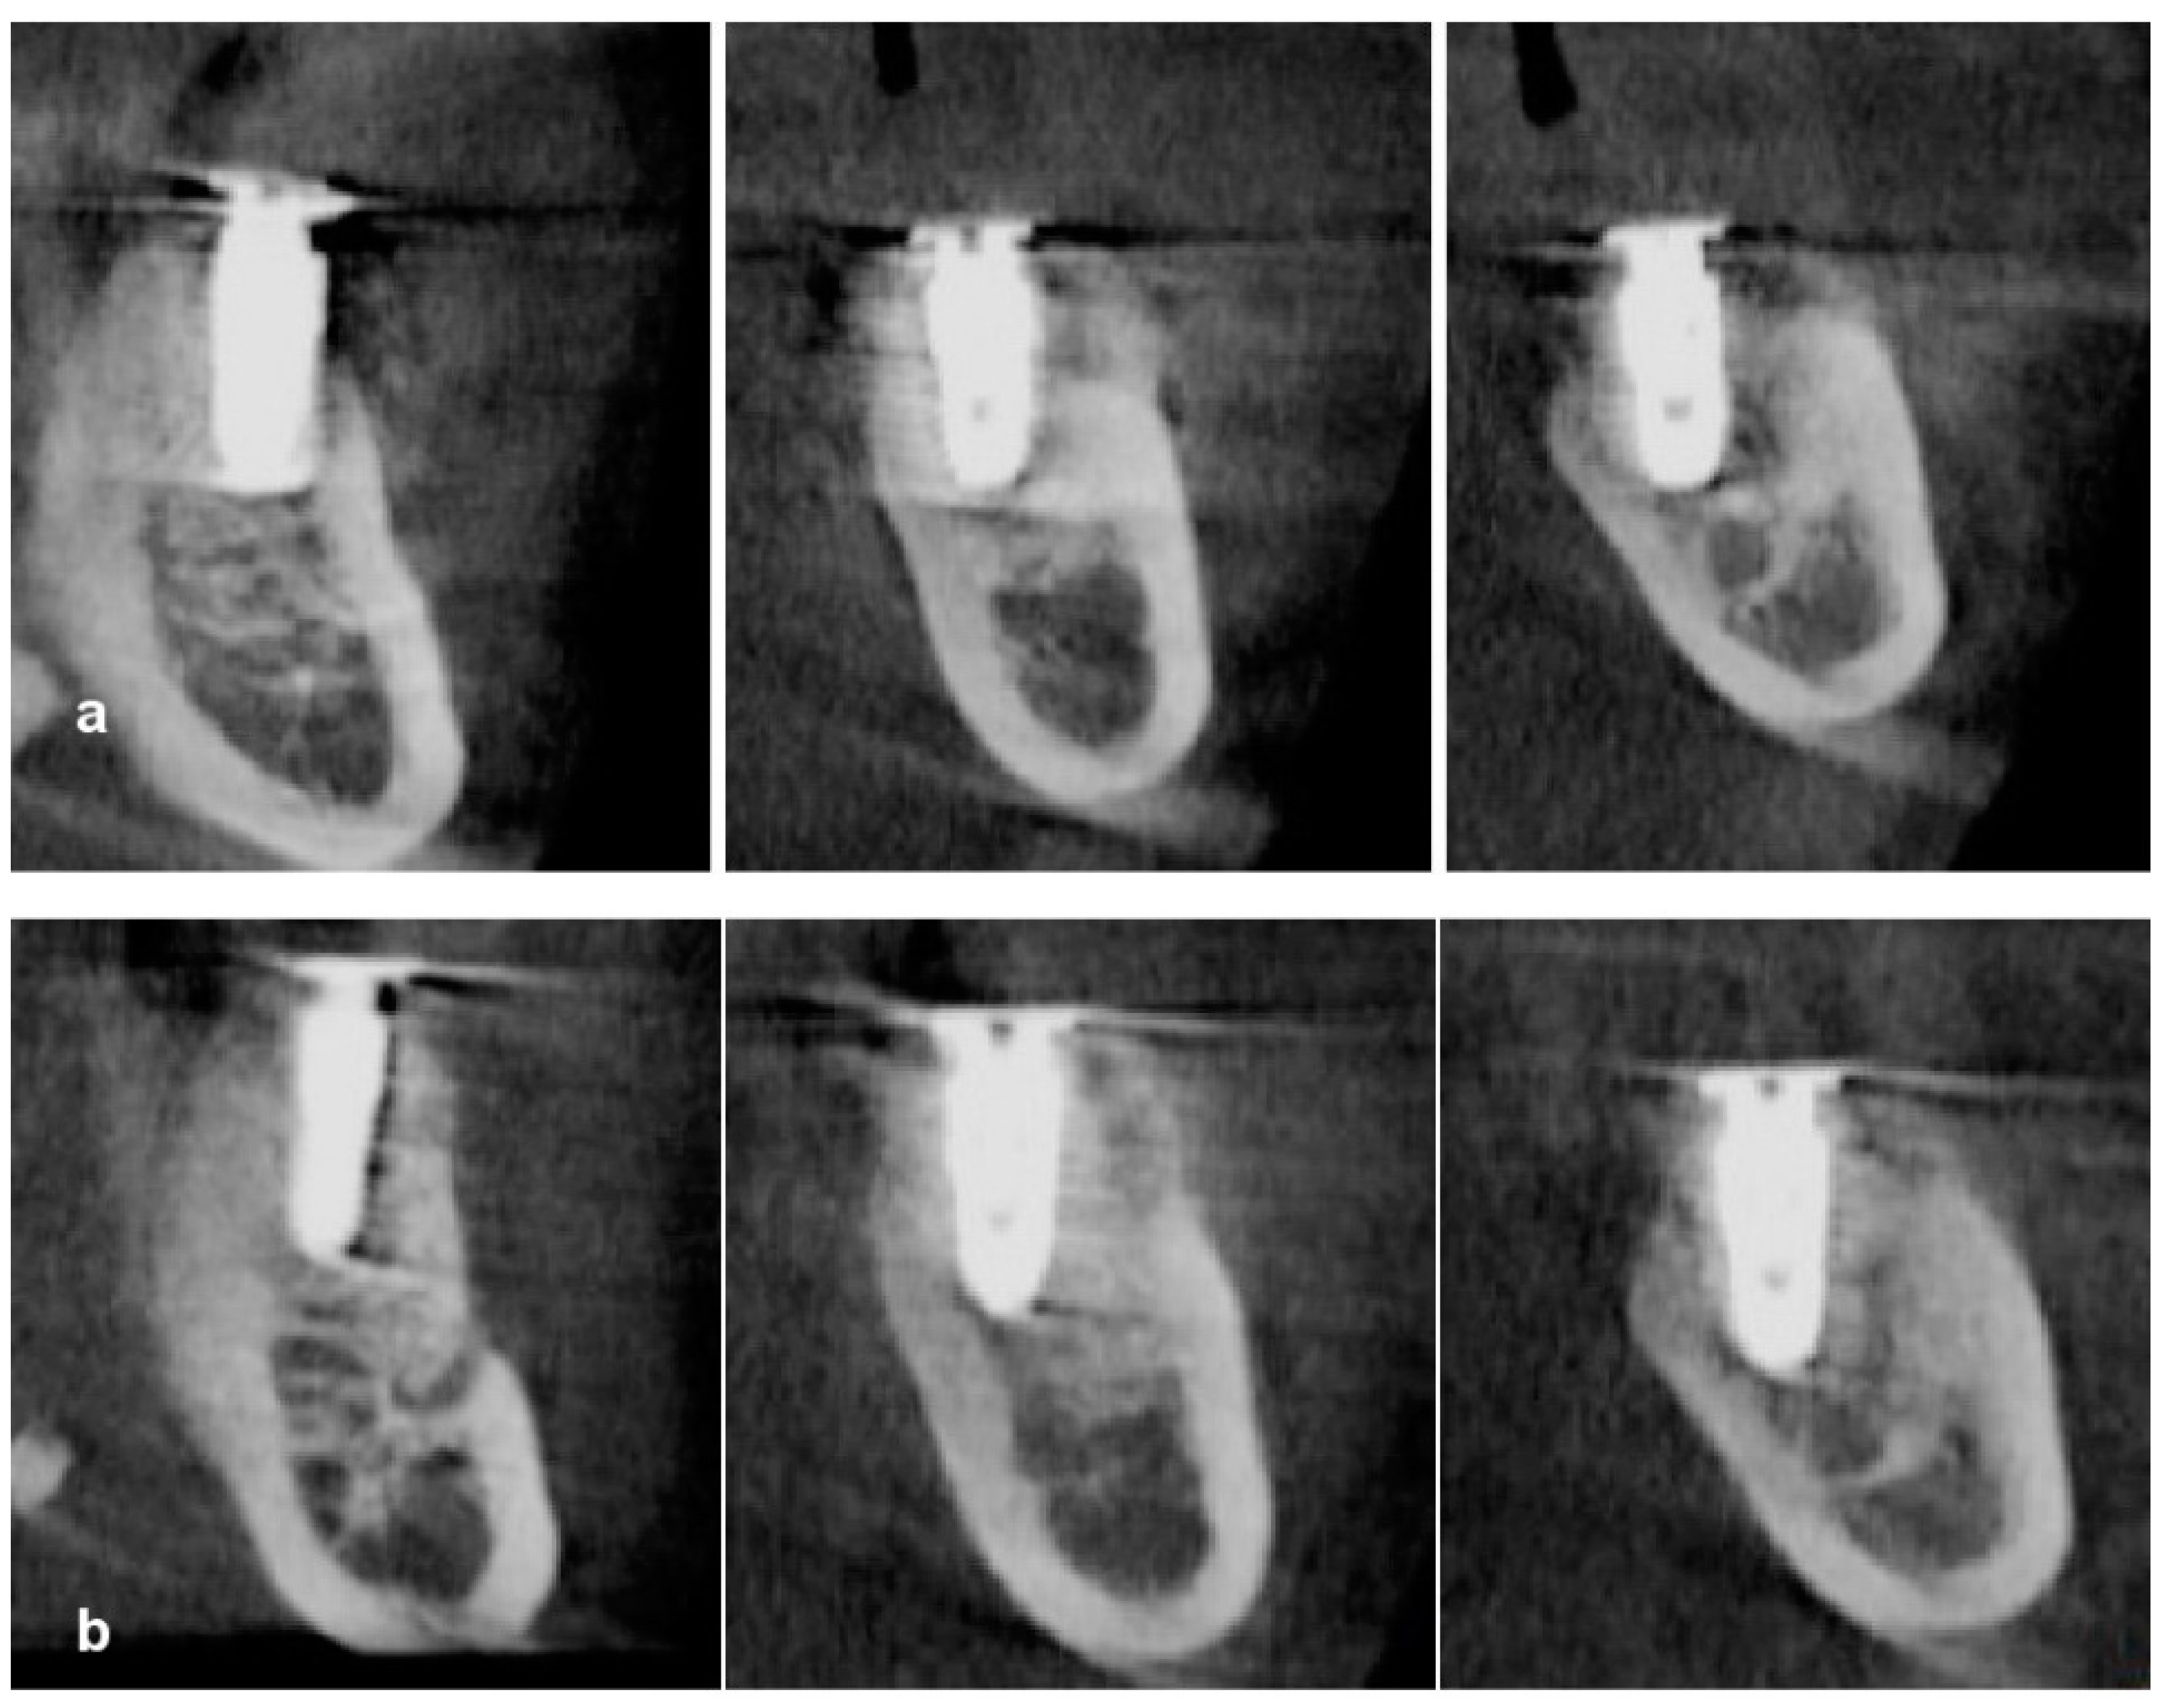

Utilization of Tenting Pole Abutments for the Reconstruction of Severely Resorbed Alveolar Bone: Technical Considerations and Case Series Reports

2. Case Presentations